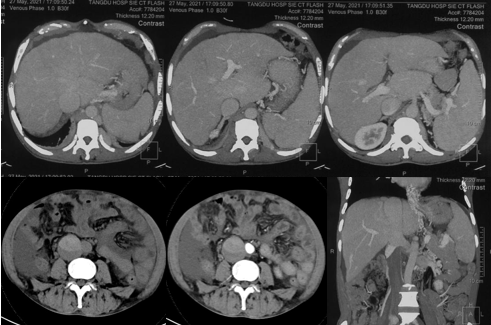

6月20日,患者及家屬懷揣著忐忑的心情來到西安國際醫(yī)學中心醫(yī)院找到韓國宏教授,韓教授詢問病情后閱患者外院CT片,明確診斷布加綜合征,同時發(fā)現(xiàn)了一個新的問題,在詢問病史時了解到患者近一周雙下肢乏力伴腫脹明顯加重,遂立即安排了急診CT,證實下腔靜脈內急性血栓形成!

6月22日,在韓國宏教授的帶領下,患者于消化介入診療中心行下腔靜脈開通術。術中可見:下腔靜脈全段擴張,膜性閉塞,腎靜脈平面以下可見血栓形成并伴有粗大的側枝靜脈,遂對狹窄段球囊擴張并植入支架,術后下腔靜脈血流通暢,側枝消失。術后第2天,患者腹壁靜脈曲張幾乎消失不見,走路也輕快了許多。明明只是薄薄的一層膜,為什么開通起來這么難?韓教授指出,盡管布加綜合征介入開通技術已使創(chuàng)傷降到了最低,但受到患者個體差異及醫(yī)療水平參差不齊的限制,仍有可能出現(xiàn)嚴重的并發(fā)癥,主要包括:心包積血、縱隔血腫、心包填塞甚至下腔靜脈撕裂引起的大出血等。而其發(fā)生率與術者的操作熟練程度及經(jīng)驗有很大的關系。